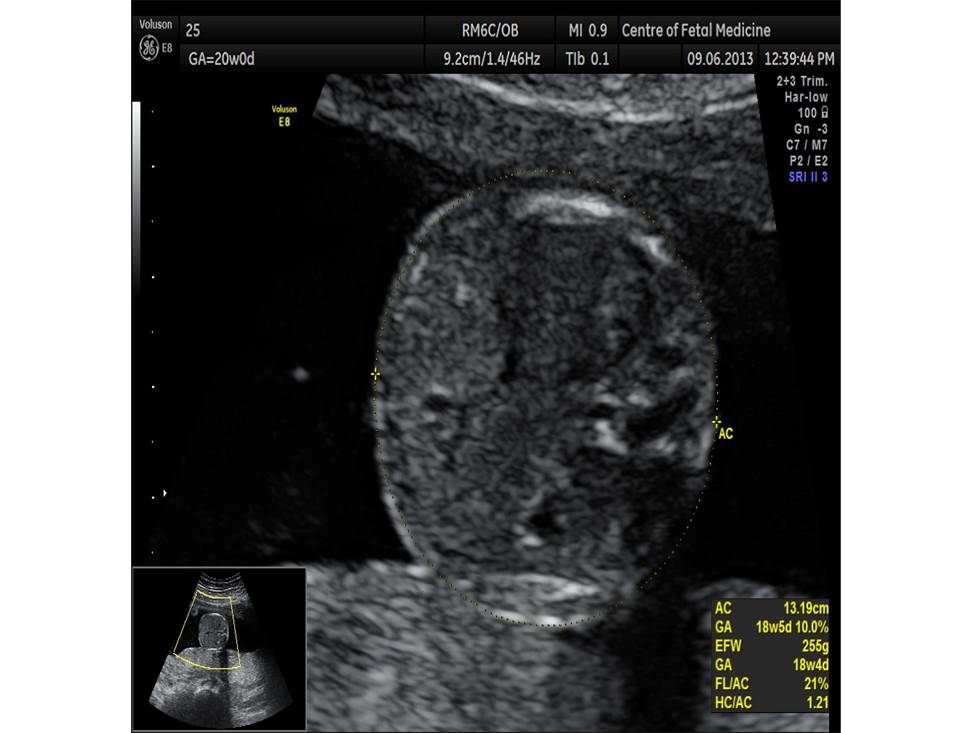

Вопрос 4

- Проанализируйте изображения плода в 20 недель, есть ли у него какие-либо маркеры хромосомной патологии?

- Необходимо ли рекомендовать инвазивную диагностику? Пациентке 25 лет, в 1 триместре не обследовалась